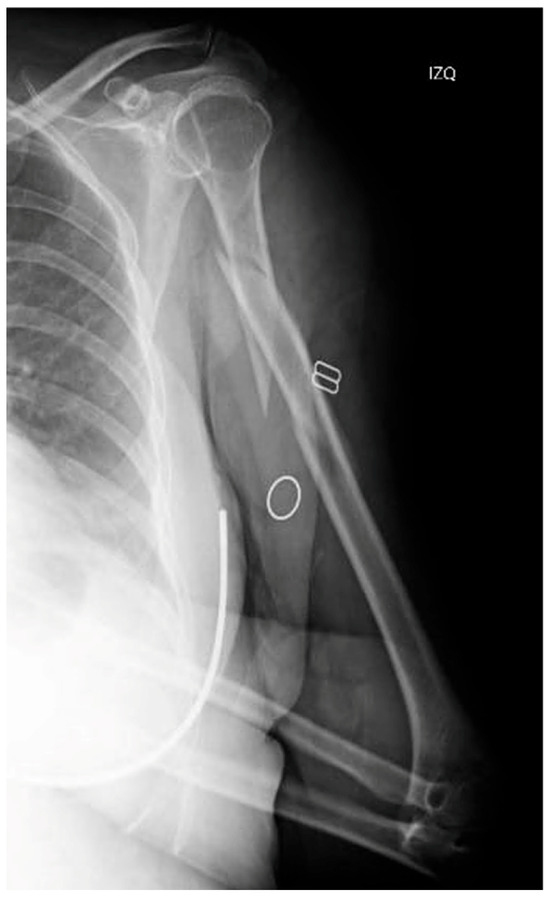

This is the case of a 62-year-old female who was admitted to our hospital following an accidental fall down the stairs that resulted in trauma to her (non-dominant) left upper limb. The patient had a history of ischemic heart disease, and her physical examination revealing pain, deformity and functional disability in the arm. A distal neurovascular examination detected no abnormalities. The radiological examination revealed an AO 12B2 segmental spiral fracture in the proximal third of the humeral shaft [4] (Figure 1).

Figure 1. X-ray of the initial injury, showing a proximal humerus fracture extending into the diaphysis.